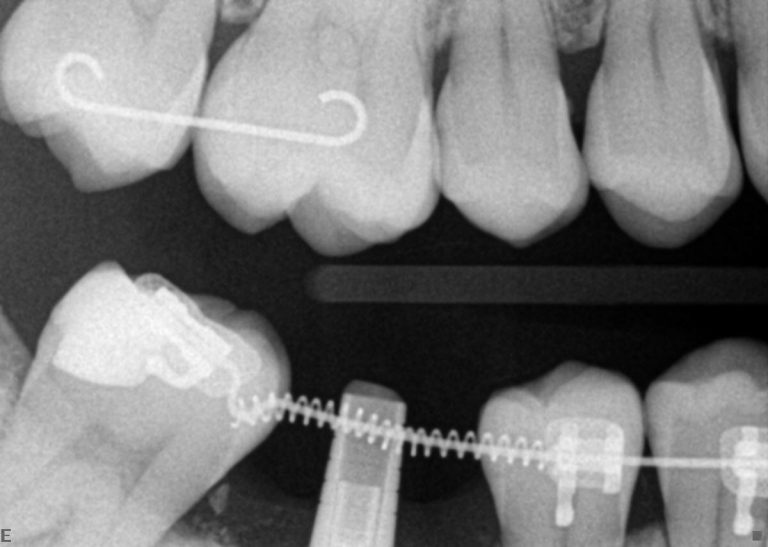

תכנון תלת ממדי של הטיפול האורתודונטי

Suresmile

שורסמייל, השיטה היחידה בה יש לאורתודונט יכולת לשלוט ולתכנן את כל התנועות האורתודונטיות בצורה מדויקת באמצעות כל סמך שהוא בוחר ובכל גישה, (סמכים חיצוניים או סמכים פנימיים או שילוב בין שיטות טיפול).

שורסמייל היא הטכנולוגיה המתקדמת ביותר שישנה כיום בעולם לתכנון מדויק ולהשגת תוצאות אופטמאליות בטיפול האורתודונטי.

שיטה זו פועלת כעשור בארה"ב.